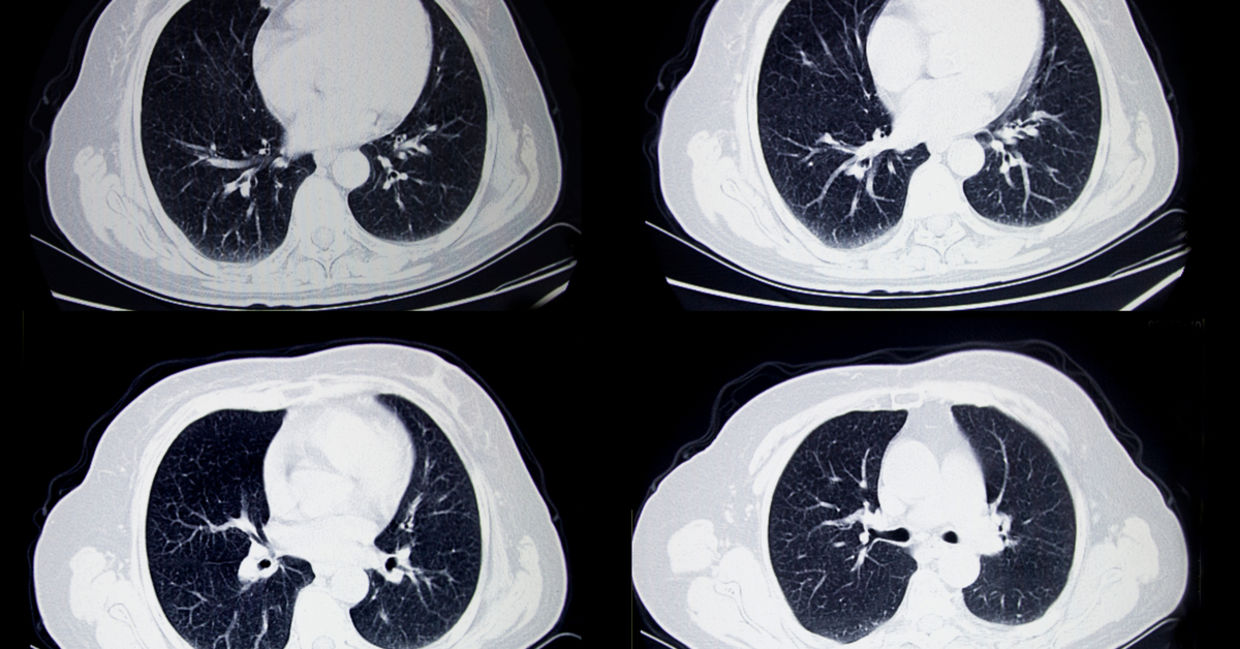

Optellum, a machine learning startup, is bringing an AI system that detects lung cancer to the masses.

The system analyzes cell clumps in scans, and Timor Kadir, the company’s chief science and technology officer, said that it could diagnose close to 4,000 patients with lung cancer per year at an earlier stage than a doctor could.

The technology would serve as a reliable tool for doctors to help them begin the healing process quicker and more efficiently, saving thousands of lives with every use.